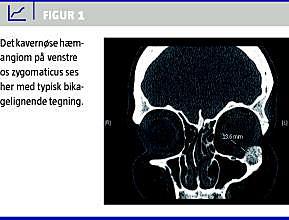

En 40-årig rask kvinde blev henvist fra privatpraktiserende otolog pga. en proces i venstre laterale orbitarand. Hun havde bemærket processen fem måneder tidligere. Patienten var symptomfri. Der var ingen dispositioner til karanomalier og intet forudgående traume mod ansigtet. Røntgenundersøgelse af ansigtsskelettet viste normale forhold ved første beskrivelse. Ved retrospektiv gennemgang af røntgenbilledet fandt man en osteolytisk rund proces på seks millimeter i diameter. To måneder senere blev røntgenundersøgelsen gentaget, og den viste nu en fire millimeter høj og ti millimeter bred, let uregelmæssig osteolytisk knogleproces på den laterale orbitakant ved os zygomaticus. Der blev efterfølgende udført computertomografi (CT), som viste en 13-14 millimeter stor knogletumor med et bikagelignende udseende (Figur 1 ). Radiologisk så tumoren benign ud. Patienten blev opereret i generel anæstesi. Tumoren blev fjernet in toto via en incision ved den nedre orbitarand. Tumoren var blålig og let blødende. Den peroperative blødning var på under 200 milliliter. Efterforløbet var ukompliceret bortset fra lidt nedsat sensibilitet over nervus infraorbitalis. Histologi viste et kavernøst hæmangiom i knoglevævet, og der var intet malignt. Man så lamellerede knoglespanger, hvorimellem der var reaktivt stroma samt talrige dilaterede karstrukturer, enlaget endotel og rigeligt blod. Der fandtes ingen elastiske fibre eller arterielignende strukturer. Ved kontrol ugen efter operationen og igen seks måneder efter var patienten velbefindende og symptomfri. Der var ikke tegn på recidiv.